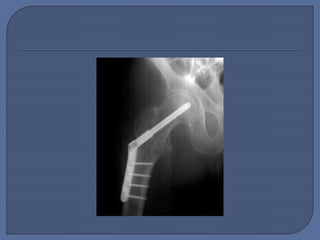

 Planning: • Nailor Screw? • Nail or screw properties  Execution: • Open • Reduce • Fix - position • Close  Tip 1: Use the Tip-to-Apex Distance  Tip 8: Avoid Varus Angulation of the Proximal Fragment—Use the Relationship Between the Tip of the Trochanter and the Center of the Femoral Head